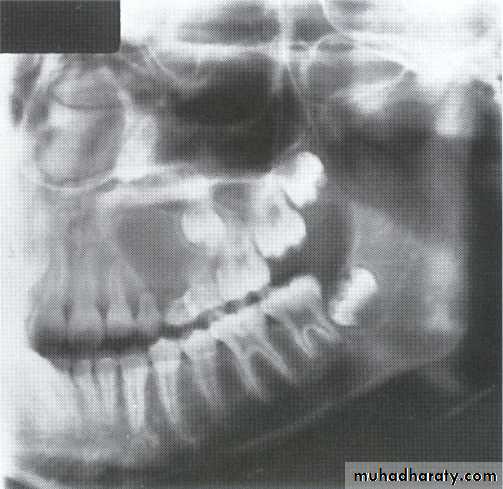

A 11-year-old female with swelling on the right side.

impacted canine

Ameloblasoma*Non-metastasizing tumor originating from remnants of the odontogenic epithelium of the enamel organ or dental lamina. *Associated with the crown of impacted teeth.

*80% located in the bicuspid & molar regions.

*Shape: is either unicystic or soap bubble-like lesion, Expansile, *Tooth migration is common,teeth in the area are vital.

*Adjacent teeth displaced, loosened , often resorbed

Extensive expansion in all dimensions

Maxillary lesions can extend into the paranasal sinuses, orbit or base of the skull.

Male > female.

Age; > 30 years